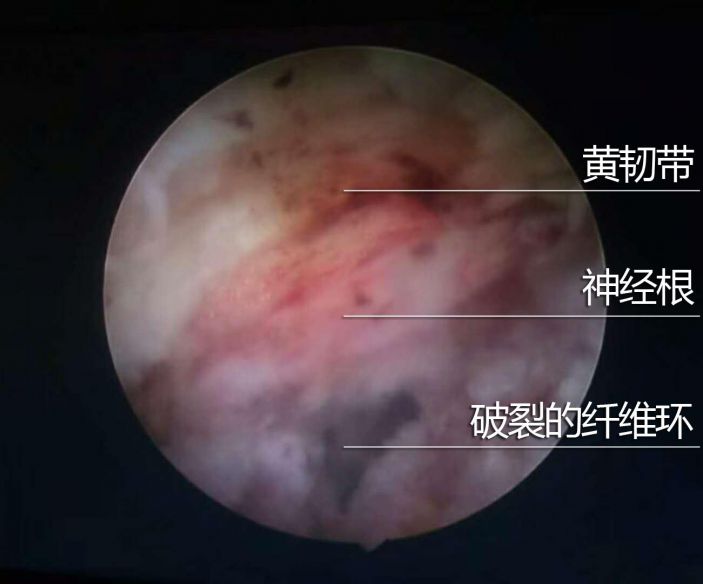

爲得到科學診治,賴某慕名于3月26日來康美醫院住院。經MRI檢查發現,患者椎間盤變性,L4/5椎間盤右後突出,右側神經根受壓。

3月28日,我院外四科吳志斌主任帶領團隊爲其實施經側路鏡L4/5椎間盤髓核摘除術。通過摘除突出髓核,解除對神經根的壓迫,達到根治目的。術後患者疼痛消失,直腿擡高試驗85度(-),手術非常成功。

據吳主任介紹,賴某的椎間盤突出并且部分疝入椎管内,壓迫神經根,神經根充血水腫,這種情況通過牽引等傳統治療難以根治,甚至還會加重病情,隻能通過手術治療。患者年紀較輕,傳統手術創傷大、出血多,術後往往加劇脊柱退變。而采用脊柱微創手術,傷口很小,隻有0.75厘米左右,術後恢複快。通過摘除突出的髓核,解除對神經根的壓迫,使神經根完全松解,手術後患者疼痛症狀即可消失,3天左右即能康複出院。